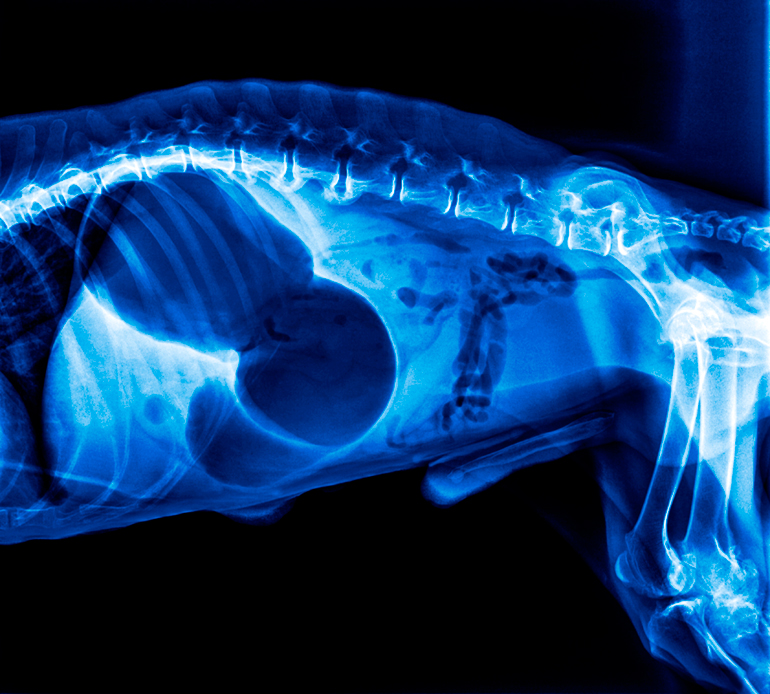

La primera medida para tratar una torsión gástrica en perros es la administración de suero a través de una vía intravenosa. Posteriormente, una radiografía constatará si se trata – en efecto- de una torsión y servirá para evaluar la gravedad del daño.